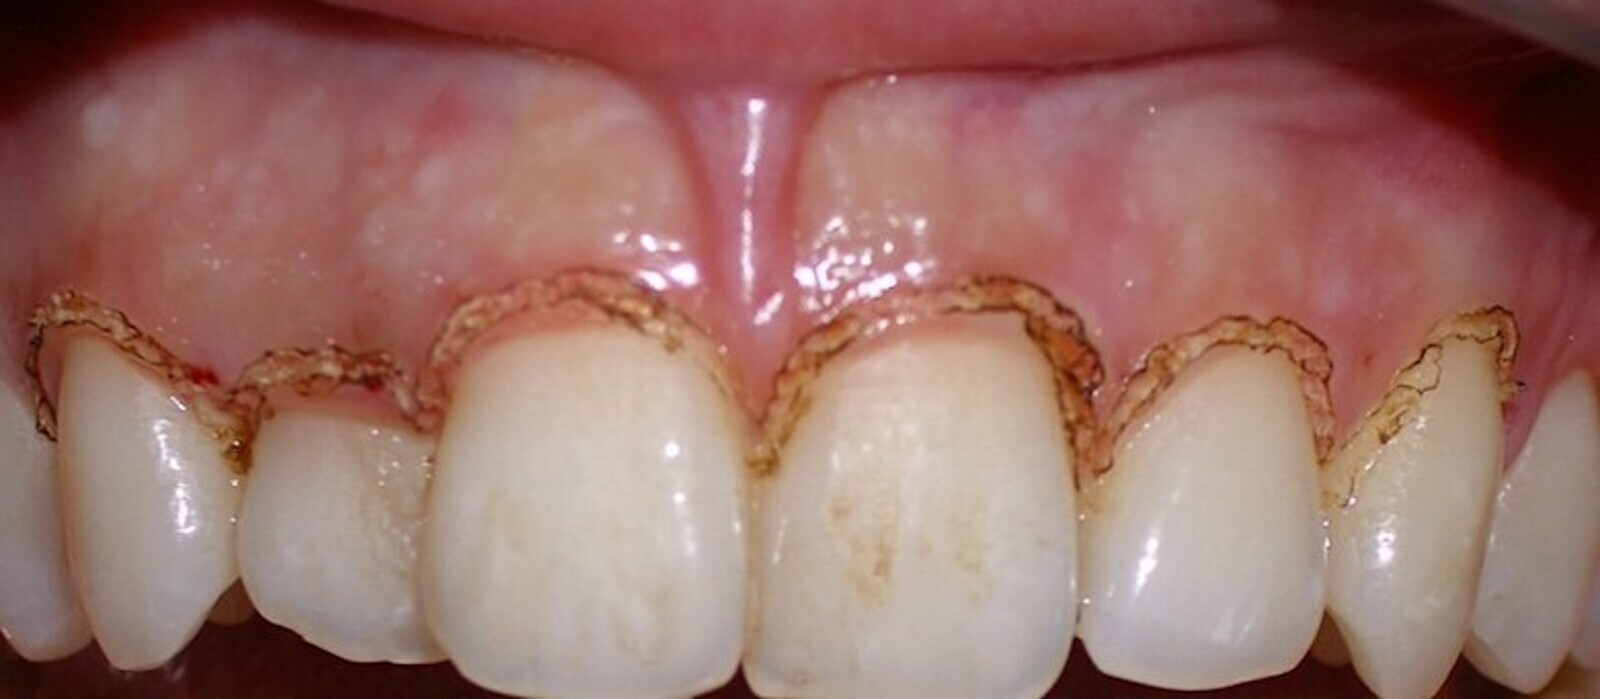

El tratamiento de estas pigmentaciones con el láser de diodo obtiene buenos resultados a nivel estético, es cómodo para el paciente durante y después de la intervención, y los resultados son muy estables a lo largo del tiempo (Figuras 6-8).

El láser de diodo obtiene buenos resultados estéticos en el tratamiento de pigmentaciones (ver Figuras 6-8).

Figura 6.

Figura 7.

Figura 8. Las figuras 6-8 muestran el tratamiento de las pigmentaciones con el láser de diodo obtiene buenos resultados a nivel estético y es cómodo para el paciente.